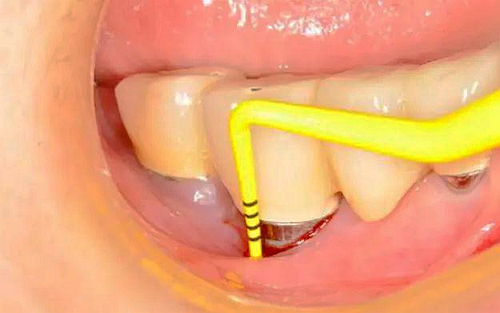

(1)去除病因:有菌斑、牙石沉積的種植體,周同黏膜探診出血陽性,無溢膿,探診深度≤4mm,應(yīng)進(jìn)行機(jī)械除菌斑治療。必須用塑料器械或與種植體同樣硬度的鈦刮治器。

(2)氯已定的應(yīng)用:在探診出血陽性,探診深度4~5mm,有或無溢膿的種植體部位,除機(jī)械治療外,還應(yīng)使用氯已定治療。